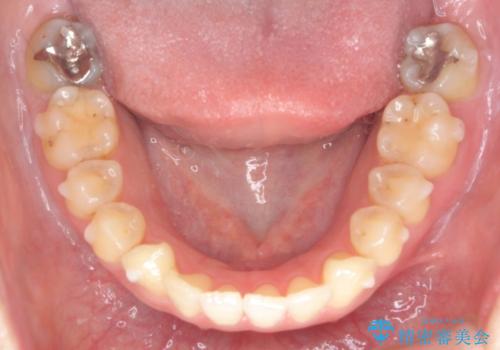

- 出っ歯に見える前歯を治したい、と矯正治療を希望され来院されました。

奥歯の噛み合わせに大きな問題はないので、目立つ前歯の角度・隙間を重点的に整え、審美的な歯並びを獲得できるよう計画します。

治療によりしっかりと前歯の角度が改善され、審美的な歯並びを手に入れることができました。